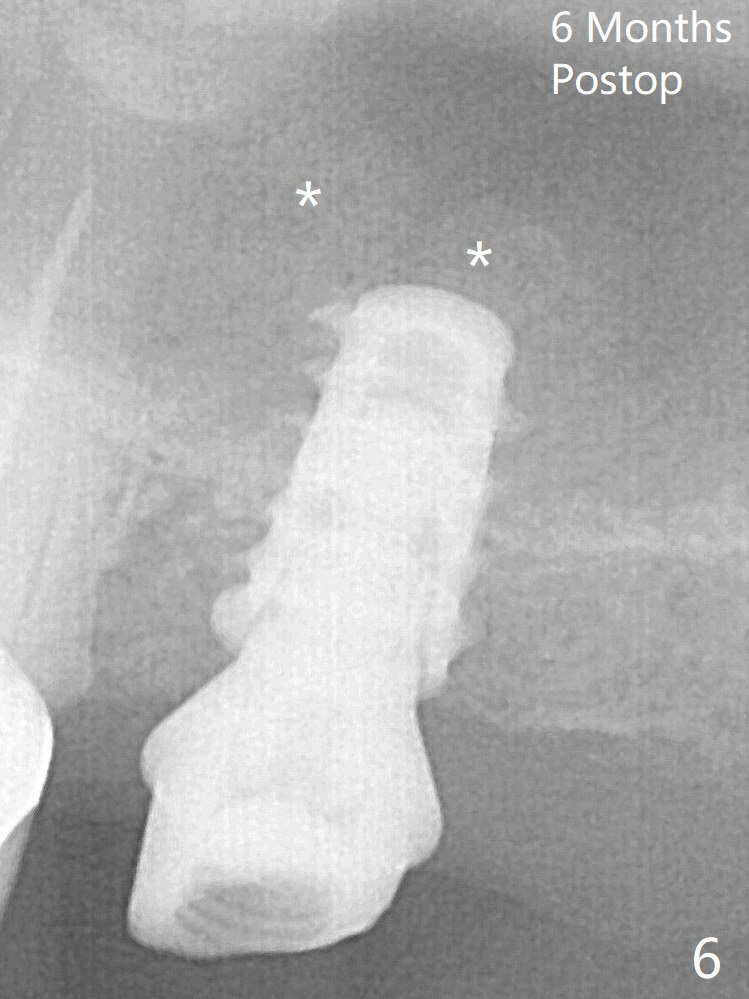

Following minimal use of Magic Lifter, Vanilla Graft is inserted (Fig.4 *) and a 4x9 mm dummy implant is placed partially.  It appears that the implant is a little too long.  After placement of more allograft (Fig.5 *), a 5x7 mm implant is placed with ~ 35 Ncm.  With placement of a 5.5x4(2) mm abutment, an immediate provisional is fabricated to close the socket.  Six months postop, the bone graft remains in the sinus around the apical end of the implant (Fig.6 *), while there seems no bone loss coronally (Fig.7).